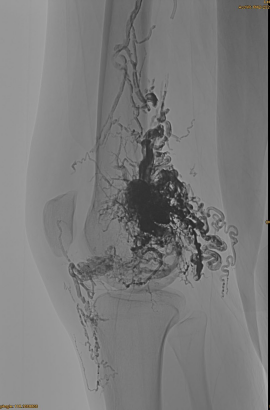

Základné informácie o pacientovi: Žena, 36 rokov; AVM Pelvis, bedra, koleno, ľavá OSG, viacnásobné predpretiek pred -.

Použité výrobky: 3ks Lava-34,14ks Lava-18.

Počiatočné DSA:

Konečný výsledok:

Sotva žiadny žilový odtok:

Neskorá fáza, ďalšia potrebná EMBO, ale oveľa lepšie: